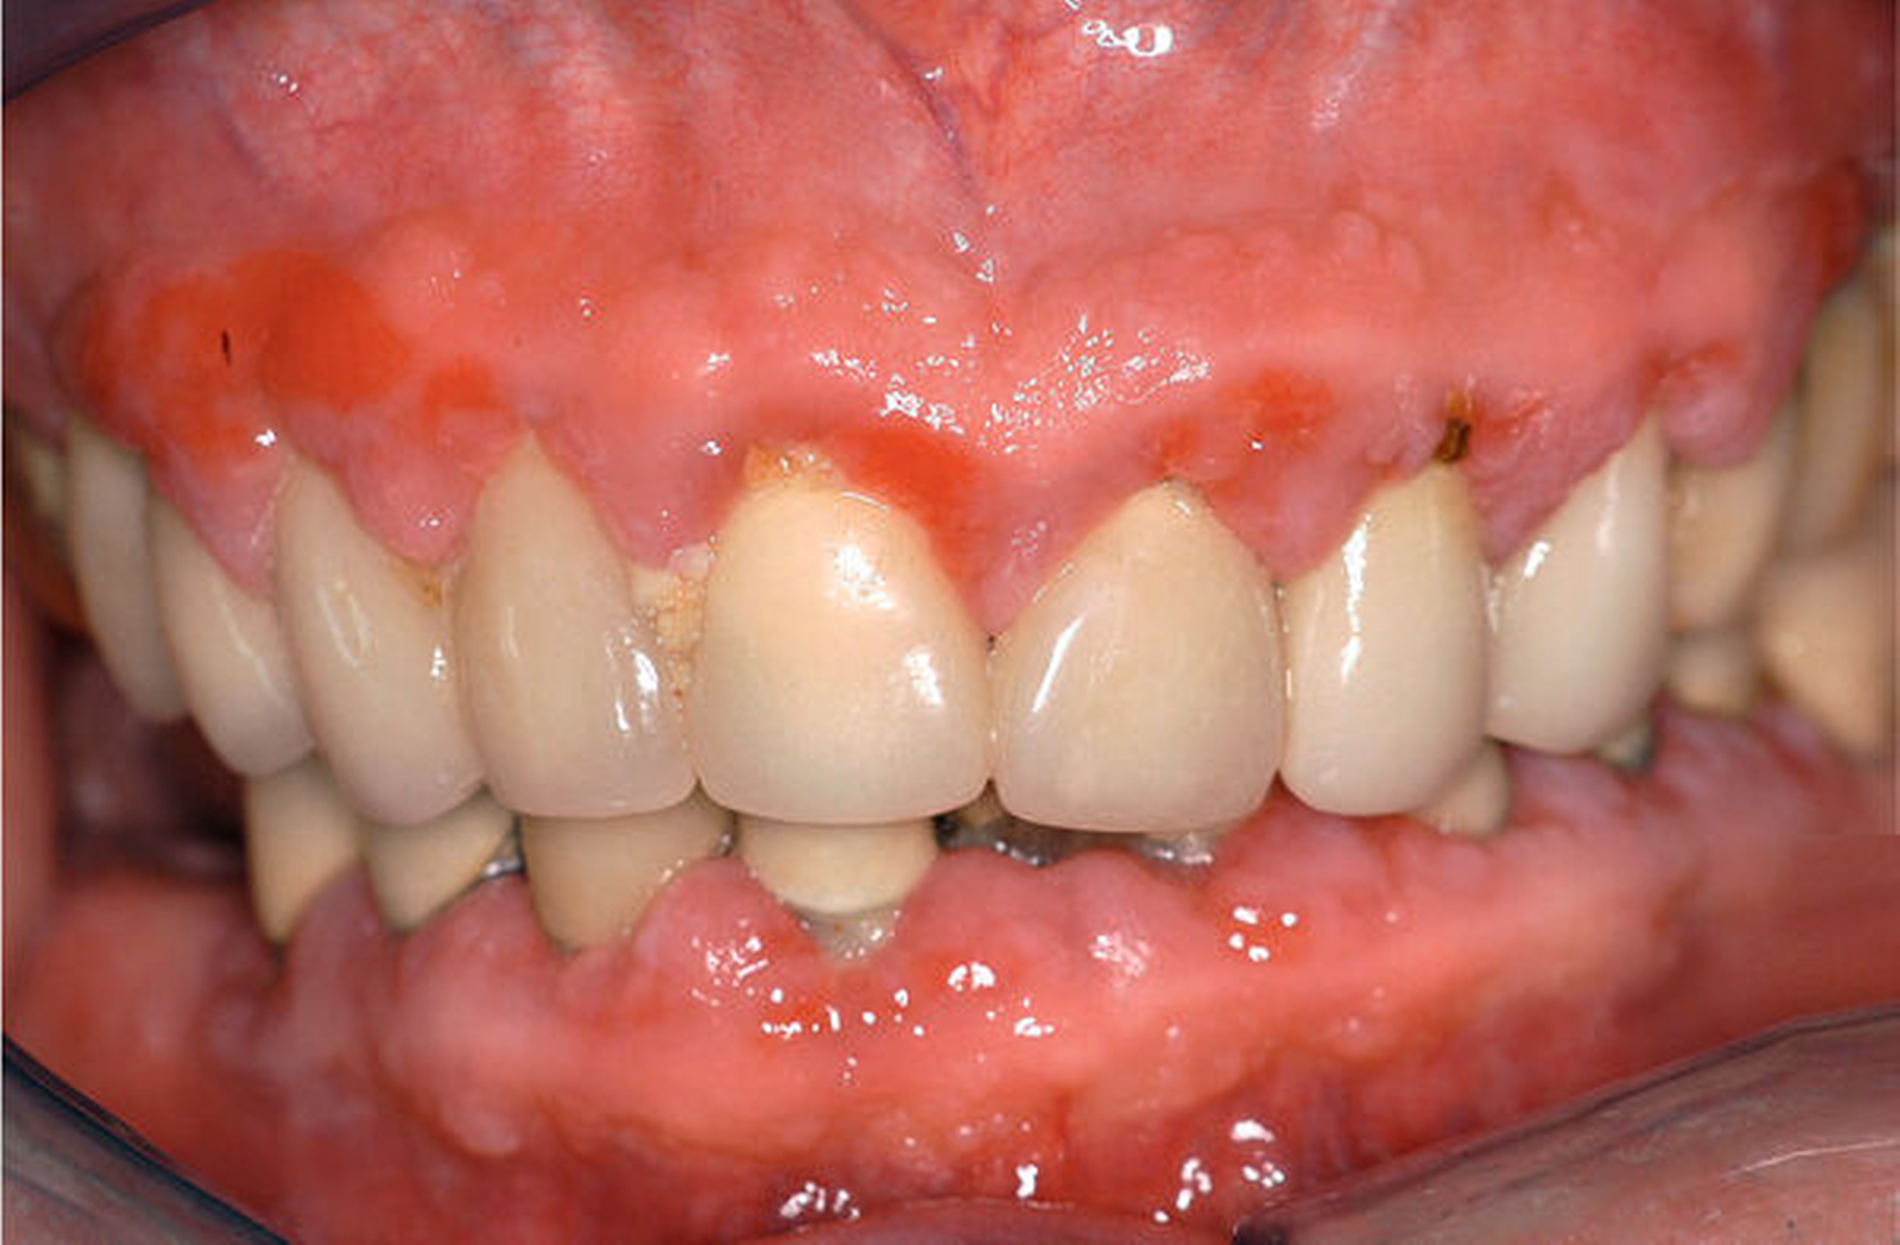

Medikamentös induzierte Gingivawucherungen

Eine weitere unerwünschte Nebenwirkung der medikamentösen Therapie kardiovaskulärer Erkrankungen sind Veränderungen der gingivalen Strukturen. Bei einer blutdrucksenkenden Medikation mit Kalziumkanal-Blockern (Nifedipin) kann es zu mehr oder weniger stark ausgeprägten gingivalen Wucherungen kommen [Hassel/Hefti, 1991] (Abbildung 3).

Die genauen Vorgänge, die zu den medikamentös-indizierten Gingivawucherungen führen, sind weitgehend unbekannt. Deren Pathogenese ist wahrscheinlich multifaktoriell. Unter dem Einfluss von Kalziumkanal-Blockern kommt es bei Individuen mit entsprechender genetischer Prädisposition nicht nur zu einer gesteigerten Matrixsynthese, sondern auch zu einer verminderten Degradation der Proteine [Kato et al., 2005; Kanno et al., 2008]. Die Entstehung und die Ausdehnung gingivaler Wucherungen sind abhängig von der Pharmakokinetik, der Dosierung sowie der Dauer der Medikation, dem zusätzlichen Gebrauch anderer Medikamente sowie der Anwesenheit harter und weicher Zahnablagerungen und dem gingivalen Entzündungszustand [Hall, 1990].